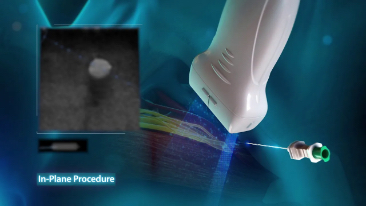

Esforzarse por una mejor atenciĂłn al paciente y buscar la mejor soluciĂłn para una decisiĂłn rĂĄpida es esencial para el personal clĂnico. Con herramientas inteligentes de gestiĂłn de fluidos, funciones para punciones seguras, una soluciĂłn completa de desinfecciĂłn e imĂĄgenes de calidad superior, el equipo Mindray TE7 ACE estĂĄ dise?ado para cubrir las aplicaciones de anestesia, cuidados crĂticos y emergencias. Listo para prestar atenciĂłn en cualquier momento, fĂĄcil de aprender y usar, ayuda a enfrentar con confianza todos los desafĂos de los servicios mĂ©dicos de alta calidad. Por primera vez, el TE7 ACE como ecĂłgrafo puede conectarse sin problemas a su red clĂnica con todos los demĂĄs equipos.